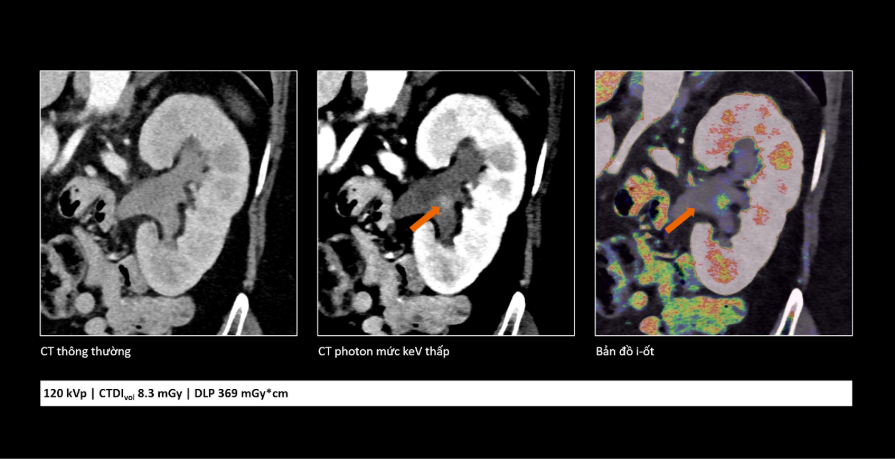

![]() |

Comparison shows photon-counting CT technology provides clearer images and additional information, supporting physicians in more accurate lesion assessment. *Photo: Siemens Healthineers* |